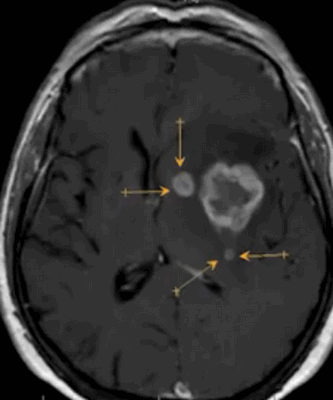

Метастазы в головном мозге на постконтрастном изображении (указаны стрелками)

Может ли МРТ показать опухоль головного мозга?

По результатам магнитно-резонансной томографии врачи могут выявить изменения структуры тканей. Опухоли головного мозга на МРТ определяют по прямым и косвенным признакам. Врачи подозревают патологическое образование по типу и равномерности изменений МР-сигнала: